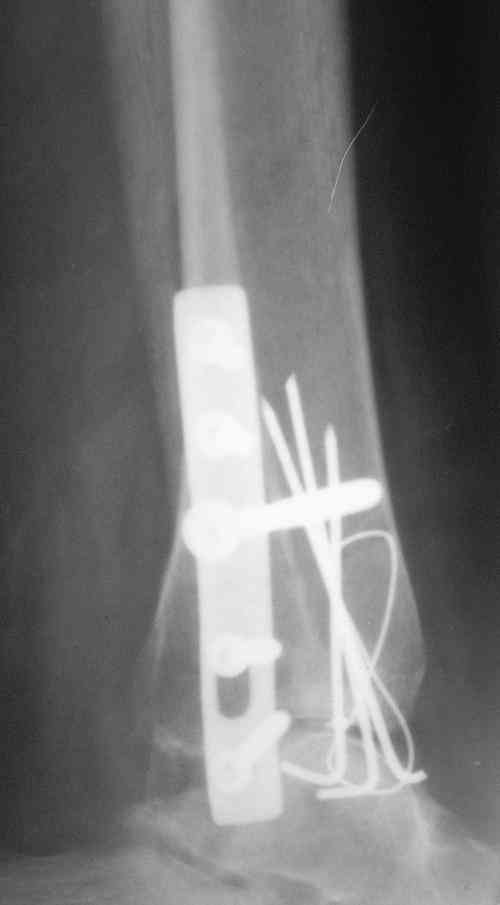

Завершая презентацию случая хотим показать результат операции. Прооперировали больную в соседнем отделении. На операции выраженый рубцовый процес в области синдесмоза, остеопоротические изменения в области медиальной и латеральной лодыжек. Провели удаление рубцовой ткани, остеосинтез медиальной и латеральной лодыжек с позиционным винтом на синдесмоз.Фото прилагаем. Благодарим за отзывы.